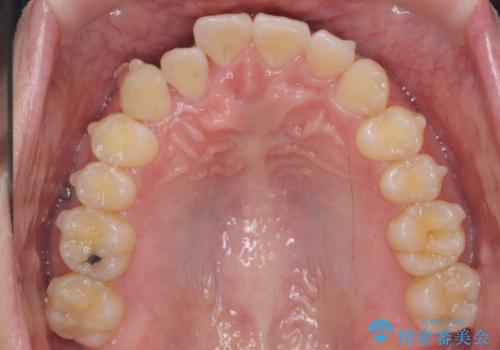

引っ込んだ前歯を並べる 歯を抜かないマウスピース矯正

- 右上の前歯が内側に入っているのを気にして来院。

右上の奥歯を後ろに移動して、前に出すスペースを確保してから並べました。

奥歯を後ろに送るために、矯正用インプラントを使用しています。

前歯が内側に入っていると、笑った時にそこが黒くなり、歯が抜けたように見えます。